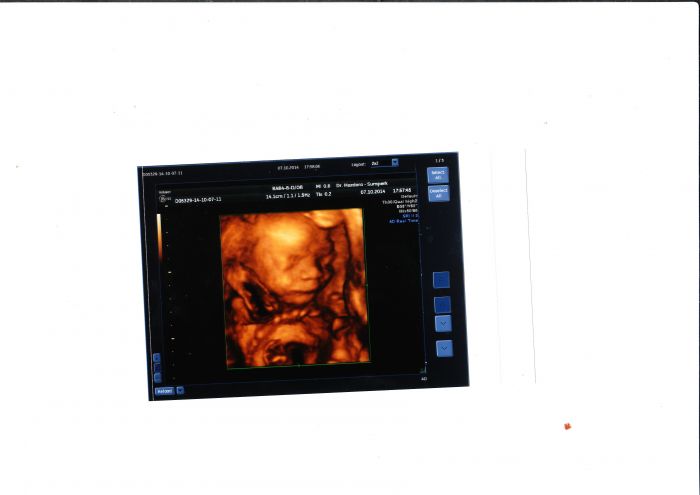

Děvčata,včera jsem byla na 4Dultrazvukovém záznamu...dala jsem za to sice 1000kč,ale to dvd(zkouknu dnes bez nastávajícího tatínka-pro něj to bude překvápko) a fotky stojí za to!!! Posílám malou ochutnávku..a přeji krásný den všem

[647928] Jee ty jsou krasny,to bude tatka koukat :) jak si tam lebedi vid ;)